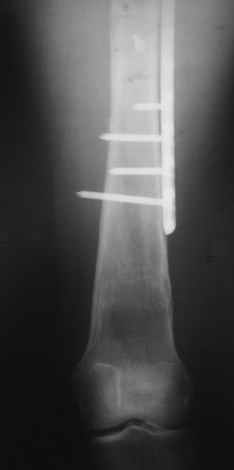

Уважаемые коллеги, приношу извенения за молчание. Готовили материал и боялись писать раньше времени. Все хотели убедиться в том, что после операции все будет спокойно. Спасибо за отклики и советы. К сожалению, гамма-гвоздя, штифтов с возможностью установки более 2-х блокирующих винтов у нас нет. Зато нашли достаточно длинную пластину с угловой стабильностью. После проведения предоперационной подготовки и планирования выполнили остеосинтез. В условиях рентгеноперационной, после репозиции дистрактором из одного разреза 5см в проксимальном отделе подкожно установили пластину. Пришлось выполнить дополнительный разрез до5см в проекции перелома диафиза в средней трети, из которого удалось репонировать перелом и выполнить фиксацию стягивающим винтом. Затем все завершилось наложением пластины с угловой стабильностью. Пластина оказалась достаточно длинной, что позволило перекрыть все переломы с фиксацией каждого отломка минимум 5-ю винтами. Синтез достаточно стабилен. Пациентка активизирована на 3-и сутки(снимки прилагаются). В настоящий момент пациентка выписана на амбулаторное лечение. Еще раз, огромное спасибо всем за помощь в выборе тактики и просто совете. С уважением Украинский Е.

Получилось очень симпатично, мои поздравления. А можно фото конечности без наклеек посмотреть?

И межфрагментарный винт на диафизе - так ли он нужен при выбранном варианте остеосинтеза с относительной стабильностью?

Хотя все-таки закрыто антгерадно заштифтовать тут было вполне можно, и при использовании отечетственного имплантата лечение обошлось бы на порядок дешевле. Опасения коллеги Кульджанова насчет кровоснабжения головки бедра и предстоящих операции в этой области кажуься несколько

преувеличенными - и стержень можно через вертел ввести, да и расстройства кровоснабжения головки, если они случатся после штифтования, не будут длиться вечно.

Но в люом случае, что сделано - то сделано, и сделанное выглядит вполне обнадеживающе, так что еще раз поздравляю коллег с успешным выходом из непростой ситуации.